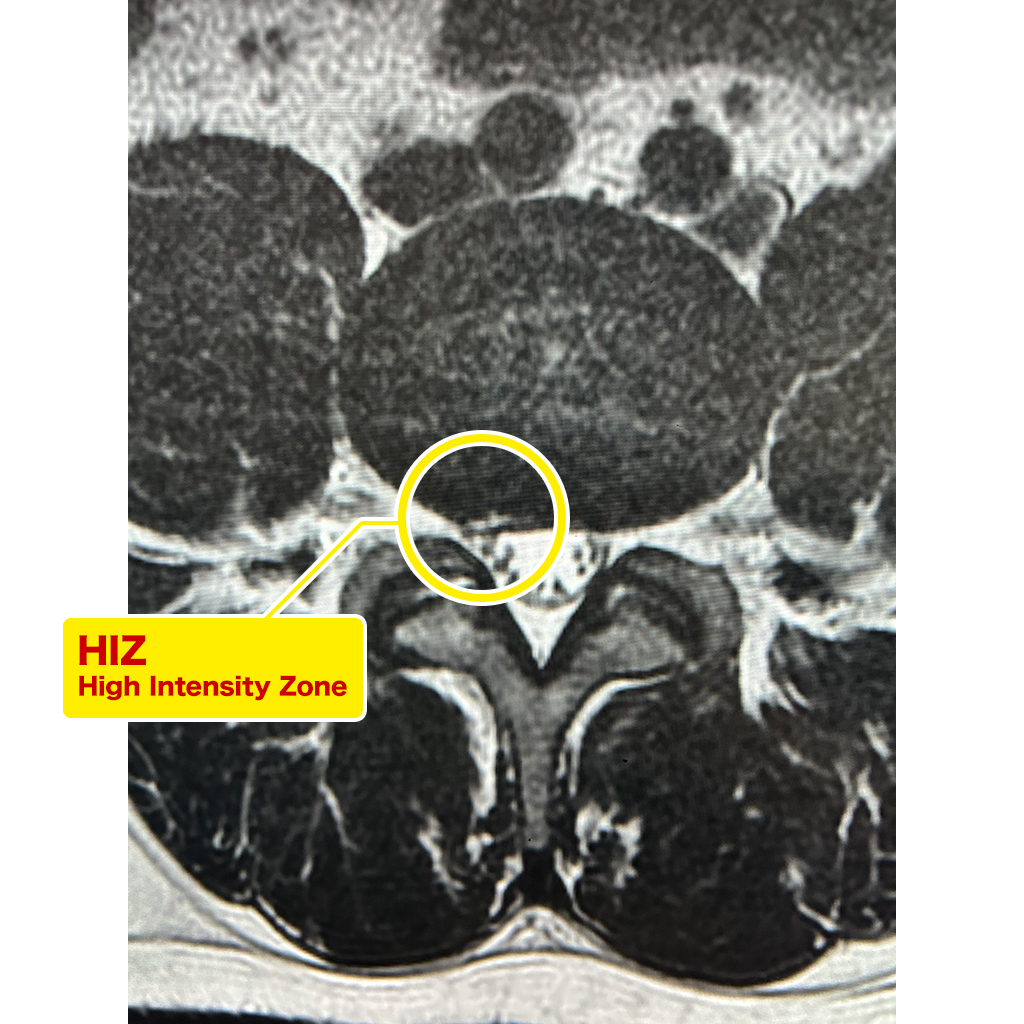

MRI検査ではL3/4、L4/5、L5/Sの椎間板変性を認め、L4/5ではHIZ(High Intensity Zone)を認めます。

椎間板の膨隆は右側に認めますが、症状は画像とは反対側の左側に認めます。

L4/5はHIZに一致した大きなリークがありました。